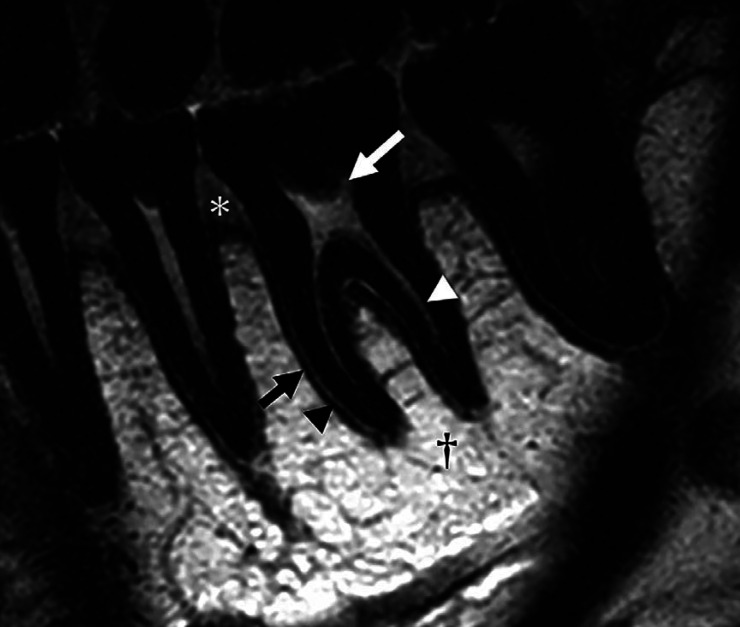

Purpose: This study aimed to assess the performance of 2-dimensional (2D) imaging with microscopy coils in delineating teeth and periodontal tissues compared with conventional 3-dimensional (3D) imaging on a 3 T magnetic resonance imaging (MRI) unit.

Materials and methods: Twelve healthy participants (4 men and 8 women; mean age: 25.6 years; range: 20-52 years) with no dental symptoms were included. The left mandibular first molars and surrounding periodontal tissues were examined using the following 2 sequences: 2D proton density-weighted (PDw) images and 3D enhanced T1 high-resolution isotropic volume excitation (eTHRIVE) images. Two-dimensional MRI images were taken using a 3 T MRI unit and a 47 mm microscopy coil, while 3D MRI imaging used a 3 T MRI unit and head-neck coil. Oral radiologists assessed dental and periodontal structures using a 4-point Likert scale. Inter- and intra-observer agreement was determined using the weighted kappa coefficient. The Wilcoxon signed-rank test was used to compare 2D-PDw and 3D-eTHRIVE images.

Results: Qualitative analysis showed significantly better visualization scores for 2D-PDw imaging than for 3D-eTHRIVE imaging (Wilcoxon signed-rank test). 2D-PDw images provided improved visibility of the tooth, root dental pulp, periodontal ligament, lamina dura, coronal dental pulp, gingiva, and nutrient tract. Inter-observer reliability ranged from moderate agreement to almost perfect agreement, and intra-observer agreement was in a similar range.

Conclusion: Two-dimensional-PDw images acquired using a 3 T MRI unit and microscopy coil effectively visualized nearly all aspects of teeth and periodontal tissues.